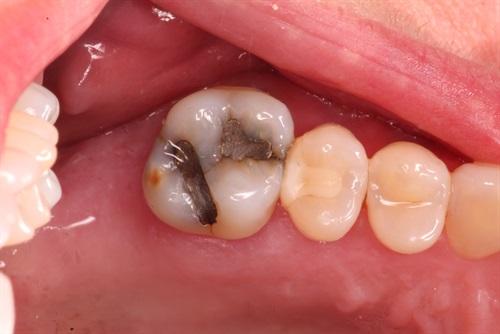

Managing fractured marginal ridge

Ribbond will not stop a tooth from fracturing but Ribbond can divert forces side ways. As a result, the tooth fractures laterally. A lateral fracture increase the odds the tooth can be restored. A vertical fracture is catastrophic.